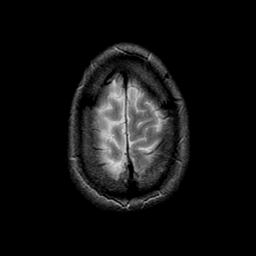

[Home][Help][Clinical] Slice 25